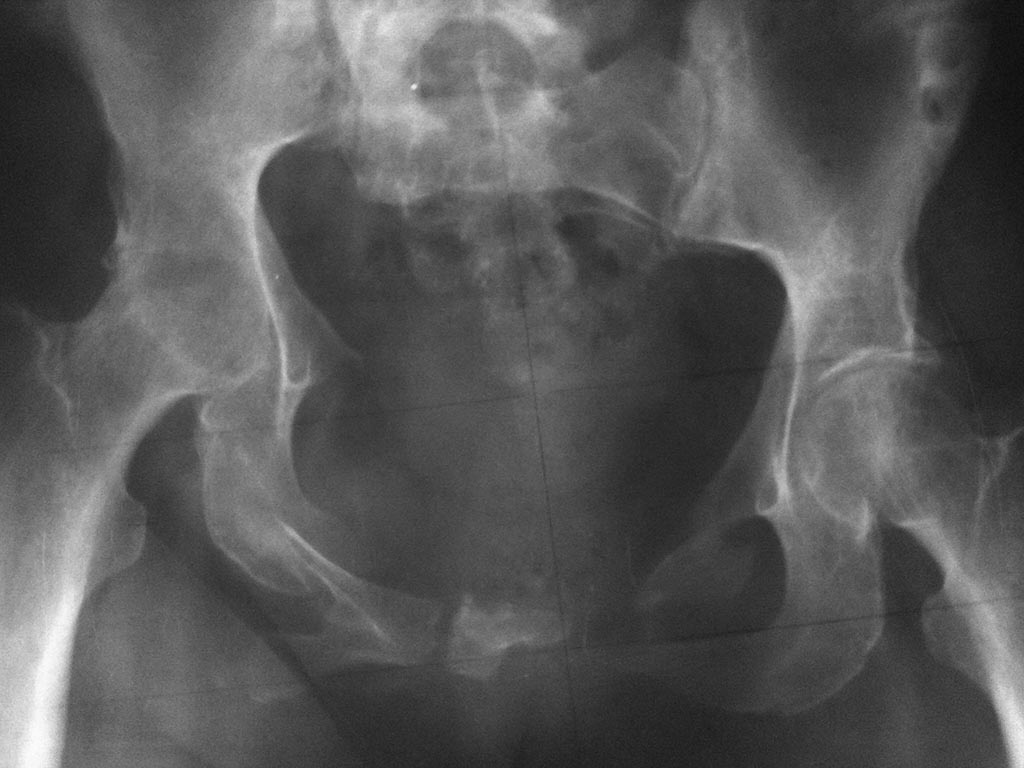

Пациентка П. 44г., травма в 2011г автодорожная. Первично - доставлена в

областную клинику, где после соответствующего противошокового лечения

(лапоротомия по по поводу разрыва мочевого пузыря) применен АВФ, который

"носила" 6 месяцев. После демонтажа перелом не сросся. В 2012г по квоте

в Кургане вновь о/синтез АВФ. Прошло 11 месяцев, неделю назад аппарат

демонтирован. На сегодня передвигается только с помощью костылей,

беспокоят боли в левом крестцово-подвздошном сочленении. Клинически:

левая нога укорочена на 5см, подвижность в левом т/бедренном суставе

отсутствует, тугая подвижность в левом крестцово-подвздошном сочленении.

На Rx таза нет сращения переднего полукольца и тугой л/сустав крестца

слева, анкилоз левого т/бедренного сустава. Учитывая молодой возраст

думаю, что пациентку можно поставить на ноги. Что делать?